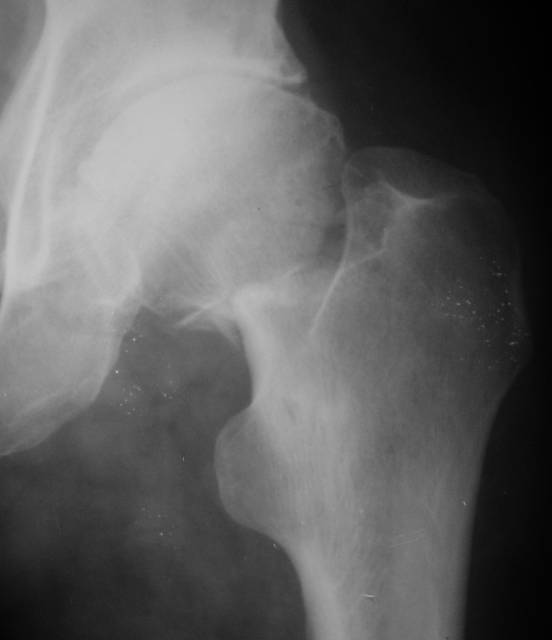

AV> опираясь на стул. На ногу не наступает. Укорочение 8 см. Иногда

А за счет чего такое укорочение? По снимку не видно соответствующего дефекта. Ну плюс приводящая контрактура - но все равно как-то уж больно много. Может, сделать снимки и таза обзорный с обоими проксимальными отделами бедра, и коенный суставов с приложенной линейкой какой?

Судя по снимку, максимум истинное укорочение около 4 см, что может быть коррегировано интраоперационно. Вопрос в другом: куда ставить ацетабулярный компонент в истинную или во вновь сформированную ( впадина диспластичная).

Невозможно не согласиться с Анатолием, чтобы заниматься адекватным планированием как минимум прямая проекция таза должна быть сделана, как

The X ray that you provided does not show 8 cm of shortening. Perhaps you could send one showing the whole pelvis and proximal femurs.

До травмы проблем с ногой не было. Укорочения, болей и т.п. не отмечал. Сегодня перемерял укорочение - меньше 7 см намерять не

получается :)

По уровню малых вертелов (с учетом рентгеновского увеличения) получается 5 см. Клинически ногу низвести путем тракции невозможно. Из движений - сгибание до 40*, остальные движения "символические".

Ортопедическое укорочение пострадавшей ноги может быть и 7, и 10 см. за счет контрактур в тазобедренном суставе, а вот истинное укорочение, судя по представленным рентгенограммам, вряд ли больше 4 см.